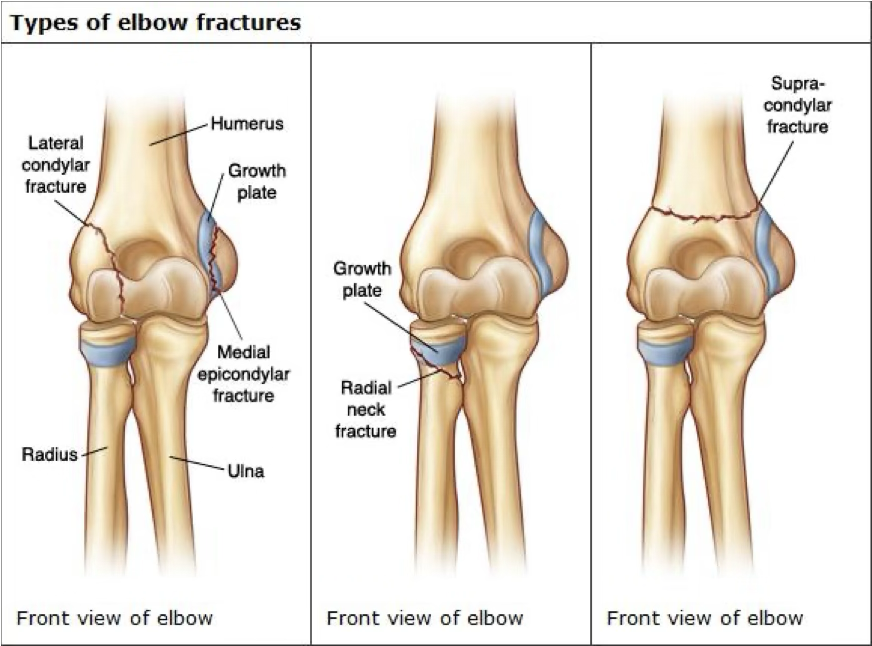

elbow fracture

FOOSH mechanism or direct hit

possible even incorrect reduction with elbow

symptoms of elbow fracture

swelling, muscle spasm, pain, possible deformity, reduced ROM, compromised neurovascular

treatment of elbow fracture

stabilize and ship

may need a sling or cast or surgery

depends on cast vs. surgery